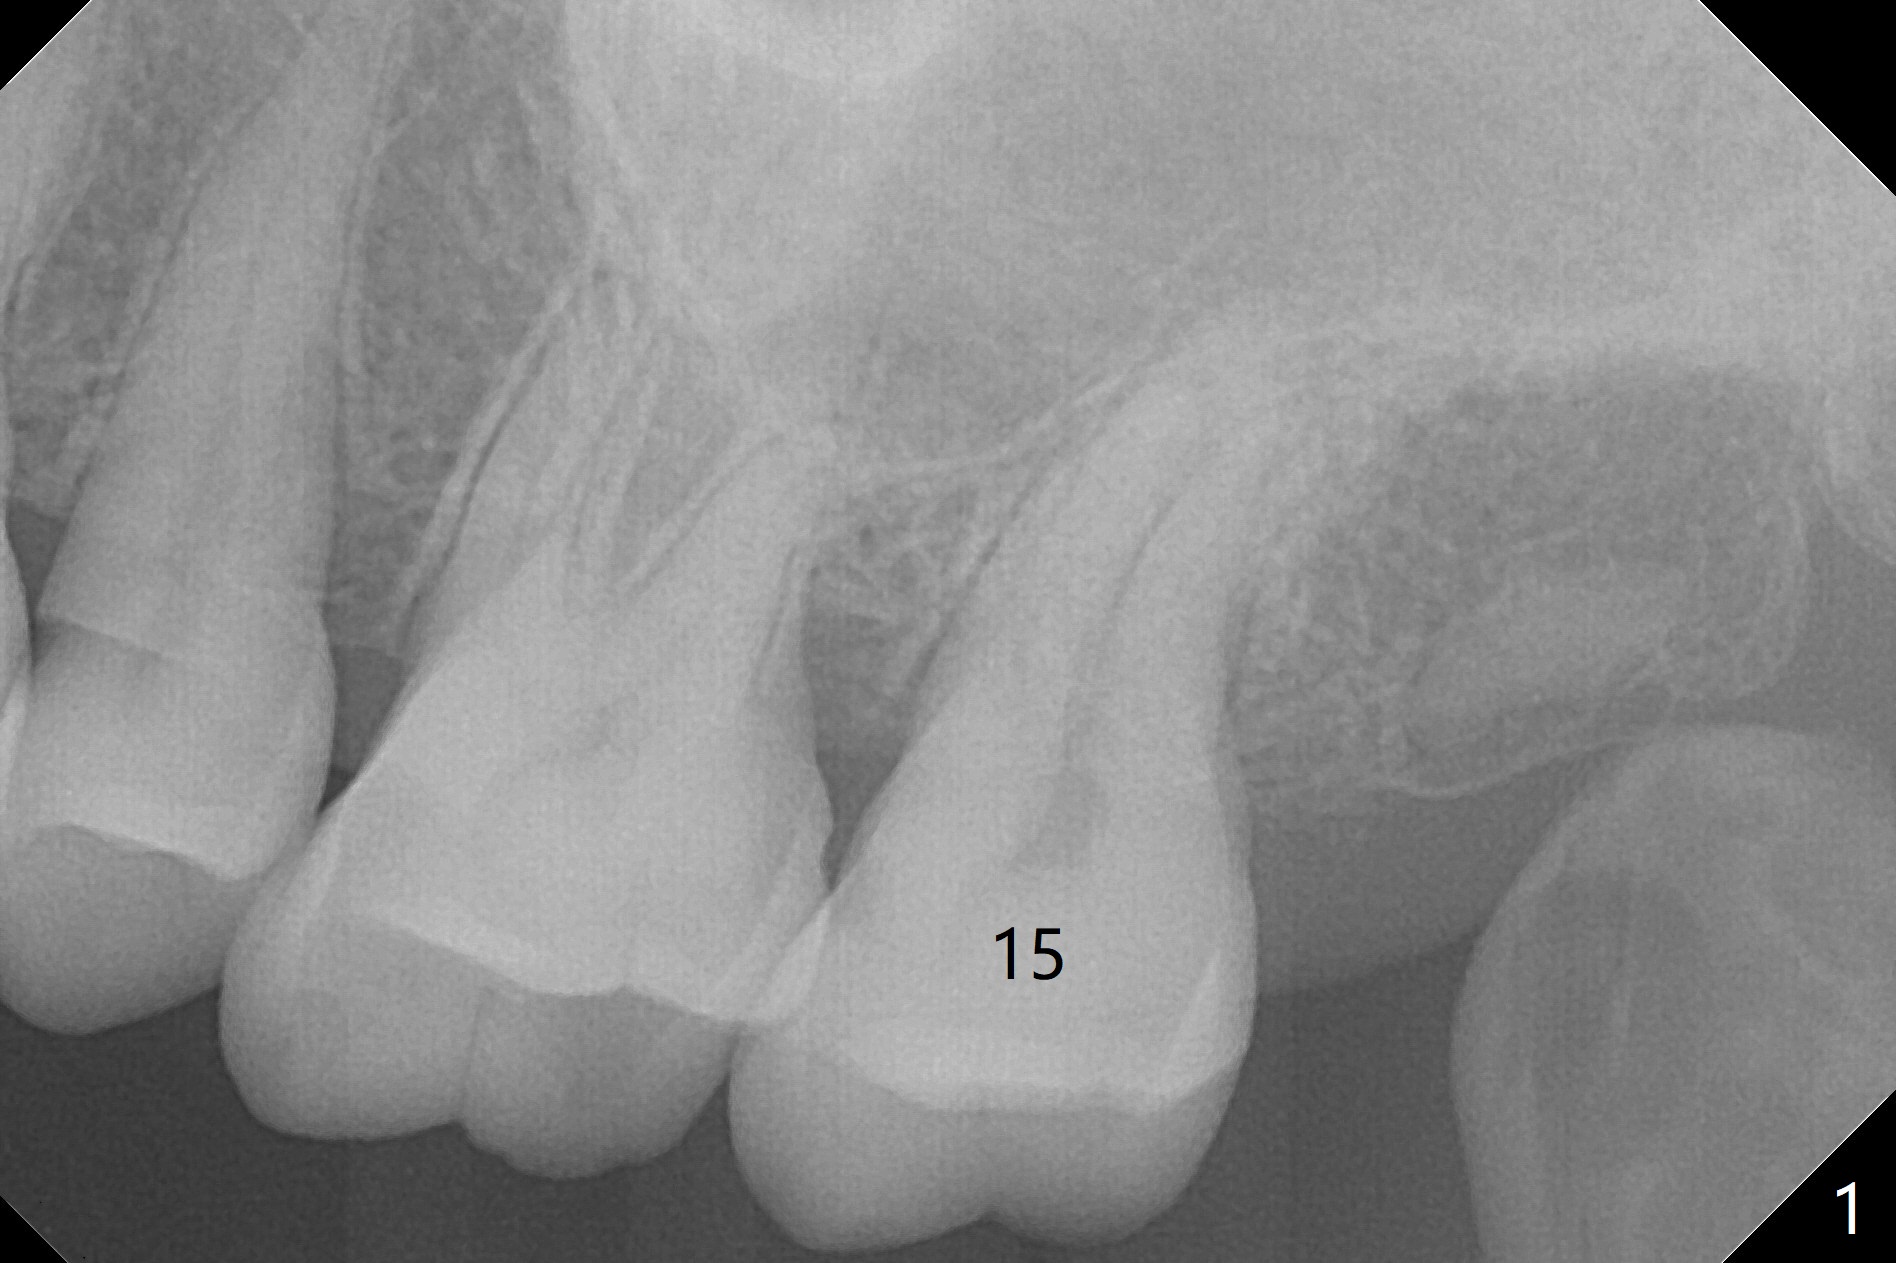

A 58-year-old woman cannot masticate on the left. The tooth #15 has a mesiodistal crack line (now completely split; take preop photo) with mild percussion and mobility I. Pulpal test shows necrosis. Although the roots seem fused and short, they are curved, suggesting bruxism (Fig.1). Use 3 mm Magic Expander to initiate osteotomy (Fig.2 green line) in the mesial slope of the socket (red dashed line). If the bone is dense, switch to Pointed/Lindamann bur. Sinus lift appears to be imminent. Draw blood before the doctor shows up. The implant will be most likely short and fat (5x8.5 mm).

Since IS implants are more or less cylindrical and if a 5 mm one does not achieve primary stability, a larger Tatum tapered tap should be tried immediately without using IS cortical taps.